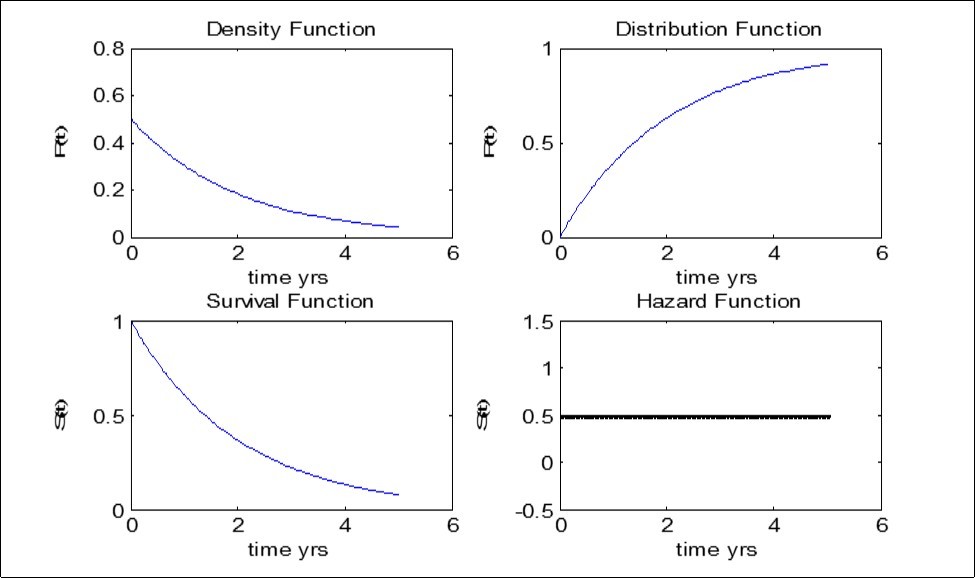

For the Weibull distribution in Figure 4, both the hazard rate and the survival rate declines monotonically with time. We can also infer that the risk of under-five mortality decreases as time increases. This will make the United Nations MDGs: to reduce under-five mortality to 2/3 by 2015 achievable.

Figure 4.Data Analysis and Validation of result - Weibull Model